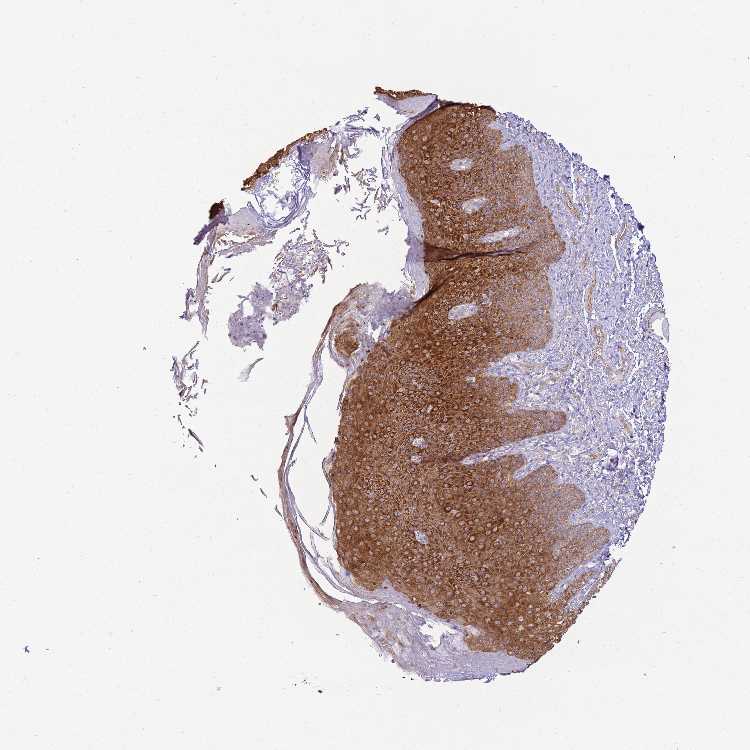

SKIN 2 - Antibody stainingi

Antibody staining in the annotated cell types in the current human tissue is reported as not detected, low, medium, or high, based on conventional immunohistochemistry profiling in selected tissues. This score is based on the combination of the staining intensity and fraction of stained cells.

Each image is clickable and will lead to virtual microscopy that enables deeper exploration of all samples and also displays staining intensity scores, fraction scores and subcellular localization as well as patient and tissue information for each sample.

Antibody HPA000497Antibody CAB004439Antibody CAB047331

Cells in basal layer --Medium

Cells in corneal layer --Not detected

Cells in granular layer --High

Cells in spinous layer --High

Endothelial cells --Medium

Epidermal cells HighHigh-

Extracellular matrix --Not detected

Fibrohistiocytic cells --Not detected

Langerhans cells --High

Lymphocytes --Not detected

Melanocytes --Medium

Vascular mural cells --Not detected